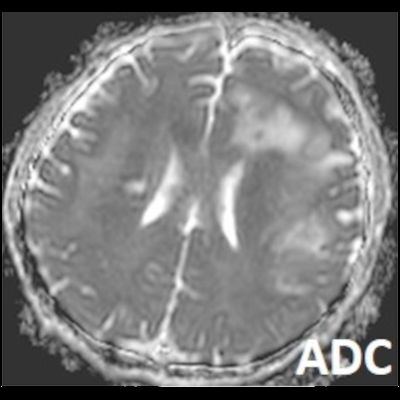

- Bilateral asimetrik subkortikal ve derin beyaz cevherde T1 ağırlıklı görüntülerde belirgin hipointens (oklar), T2A görüntülerde hiperintens (oklar), gri cevhere bakan kesimi düzgün (oklar), DAG’de hiperintens (ok) lezyonlar izlendi. Lezyonlarda T2/FLAIR uyumsuzluğu vardı (ok). Serebellar beyaz cevherde dentat nukleusu koruyan hilal işareti görüldü (ok başı). SWI sekansta sol motor kortekste hipointens kronik glioinflamatuar reaksiyon ile uyumlu sinyal değişikliği izlendi (ok başı).

- PML lezyonları, T1A görüntülerde belirgin hipointenstir. Gri cevhere bakan yüzleri keskin olup T2/FLAIR uyumsuzluğu önemli özelliğidir.